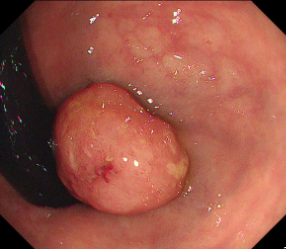

Polyps are early cancer indicators, so assessing occurrences of polyps and their removal is critical. They are observed through a colonoscopy screening procedure that generates a stream of video frames. Segmenting polyps in their natural video screening procedure has several challenges, such as the co-existence of imaging artefacts, motion blur, and floating debris. Most existing polyp segmentation algorithms are developed on curated still image datasets that do not represent real-world colonoscopy. Their performance often degrades on video data. We propose a video polyp segmentation method that performs self-supervised learning as an auxiliary task and a spatial-temporal self-attention mechanism for improved representation learning. Our end-to-end configuration and joint optimisation of losses enable the network to learn more discriminative contextual features in videos. Our experimental results demonstrate an improvement with respect to several state-of-the-art (SOTA) methods. Our ablation study also confirms that the choice of the proposed joint end-to-end training improves network accuracy by over 3% and nearly 10% on both the Dice similarity coefficient and intersection-over-union compared to the recently proposed method PNS+ and Polyp-PVT, respectively. Results on previously unseen video data indicate that the proposed method generalises.